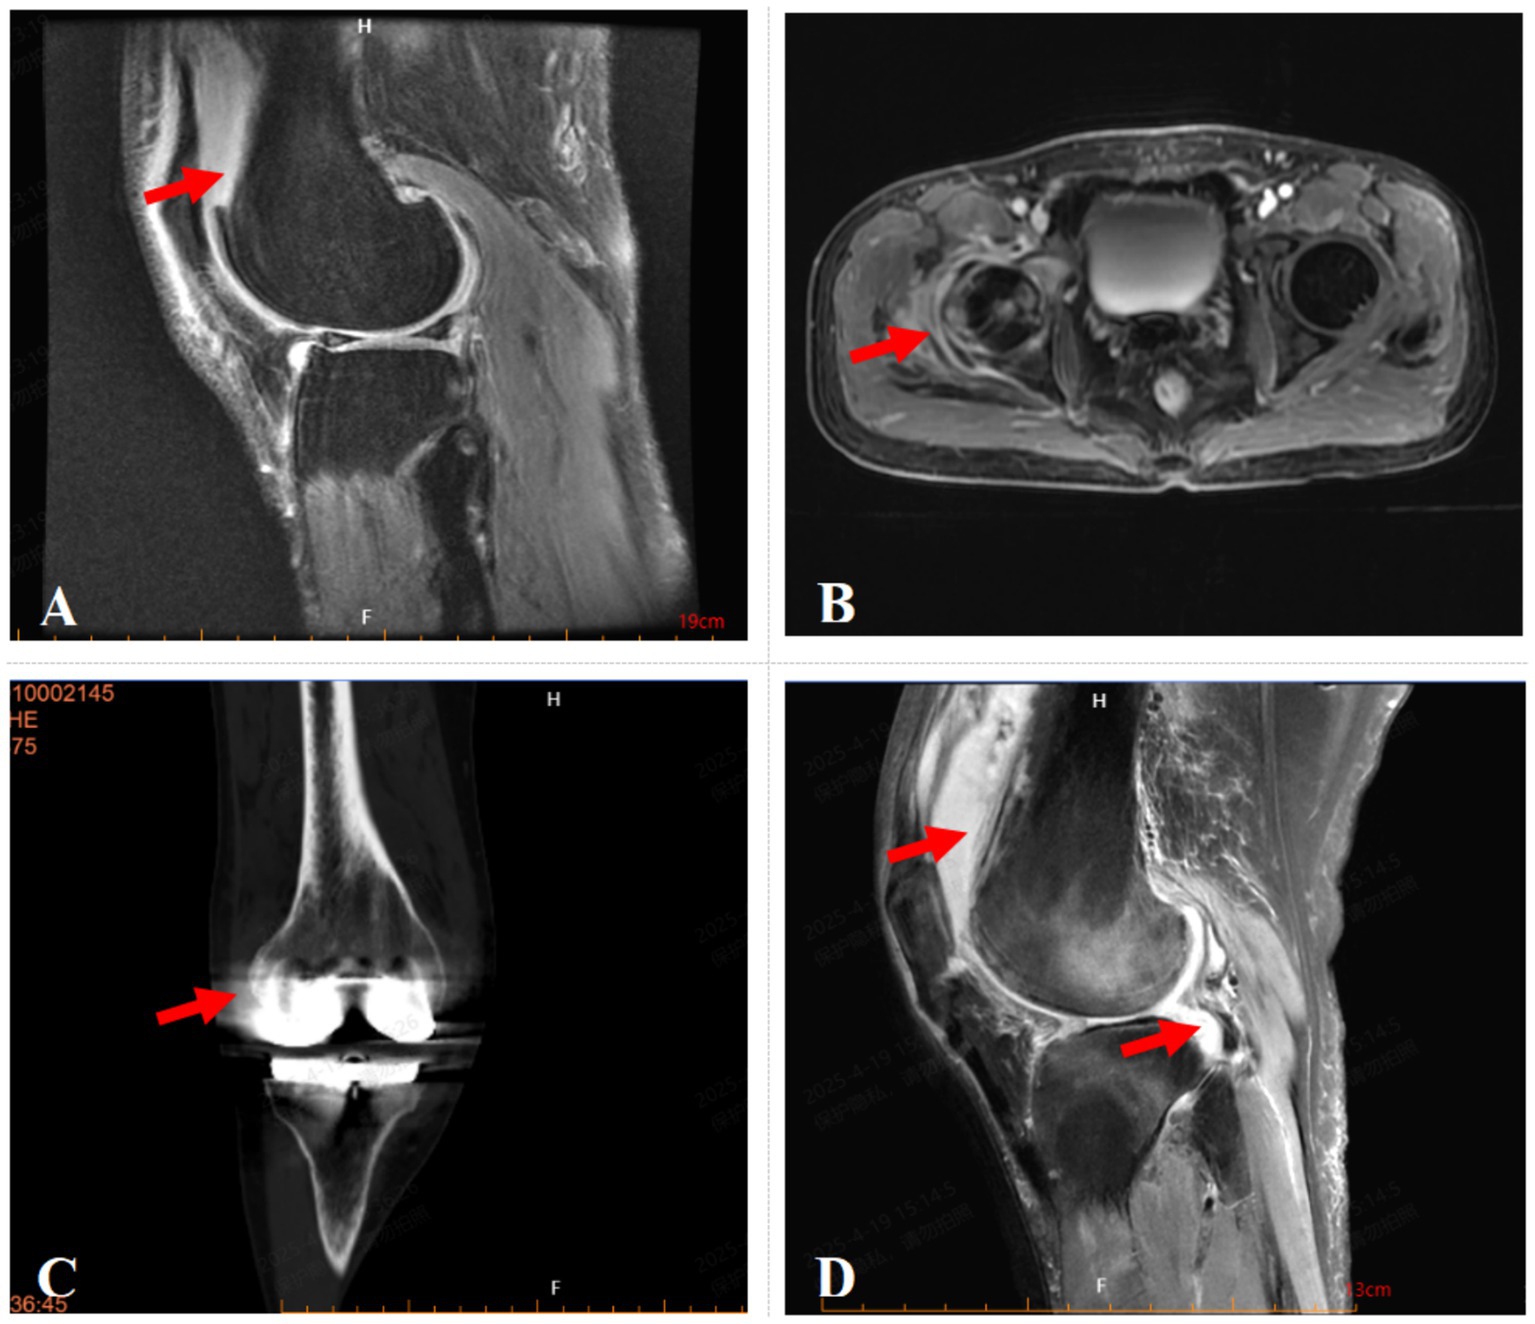

A 55-year-old male farmer presented with a history of right knee pain and weakness persisting for three years, exacerbated by physical exertion. The symptoms were significantly aggravated following an accidental right knee sprain two weeks prior to admission. On April 26, 2022, the patient was hospitalized with a diagnosis of severe osteoarthritis of the right knee joint. Clinical examination revealed a normal body temperature (37 °C), knee joint swelling, localized skin temperature elevation, and a 5° varus deformity. Tenderness was noted on the anteromedial aspect of the right knee, with restricted flexion-extension range (5°–90°) and a positive patellar ballottement test. Magnetic resonance imaging (MRI) demonstrated injuries to the medial and lateral menisci, patellar ligament, anterior and posterior cruciate ligaments, and medial and lateral collateral ligaments. Additionally, osteochondral damage and bone marrow edema were observed in the medial femoral and tibial condyles, accompanied by subcutaneous edema on the anterolateral knee and effusion in the joint cavity and suprapatellar bursa (Figure 1A). Laboratory findings shows elevated white blood cell count (WBC) and C-reactive protein (CRP) level, along with increased erythrocyte sedimentation rate (ESR), indicate significant inflammation, possibly suggestive of septic arthritis (Table 1). While joint fluid culture (bioMérieux blood culture system) was negative, mNGS identified Brucella (14 reads), and the Brucella agglutination test yielded a positive result. Following confirmation of Brucella joint infection, the patient was transferred to Jinan Infectious Disease Hospital for subsequent treatment. The six-month follow-up showed that the patient has recovered well.

Figure 1

Imaging of the affected joints in four patients. (A) Fat-suppressed MRI image of case 1 shows anterolateral subcutaneous edema and suprapatellar bursal effusion. (B) Contrast-enhanced MRI image of case 2 demonstrates abnormal signal intensity with restricted diffusion and enhancement in the periaritcular soft tissues of the right hip, suggestive of inflammation with abscess formation. (C) CT image of case 3 shows Knee Prosthesis and swelling of the periarticular soft tissues. (D) Fat-suppressed MRI image of case 4 shows joint effusion and suprapatellar bursal fluid with periarticular soft tissue edema.

A 42-year-old male farmer presented with a 37-day history of right hip injury sustained during heavy lifting, accompanied by progressive limitation of right hip joint mobility. The patient was admitted on December 4, 2023, due to worsening hip pain. Initial physical examination revealed normal body temperature (36.6 °C), tenderness upon percussion of the right greater trochanter, positive tenderness at the midpoint of the right inguinal region, restricted right hip joint mobility, a positive right “4” sign, and intact sensation and muscle strength in both lower limbs with normal dorsalis pedis artery pulsation. MRI demonstrated bone marrow edema in the right femoral head and acetabulum, soft tissue edema surrounding the right hip joint, and bilateral hip joint effusion (Figure 1B). Laboratory investigations revealed elevated inflammatory markers, including WBC, CRP and ESR, indicate significant inflammation which possibly caused by infection (Table 1). Empirical antibiotic therapy with moxifloxacin was initiated. Subsequent diagnostic evaluations, including joint fluid and blood cultures, yielded negative results, and the Brucella agglutination test was also negative. However, mNGS of the joint fluid identified Brucella species (reads: 5,021). Considering the patient’s occupational exposure to cattle and sheep, a definitive diagnosis of Brucella joint infection was established. The patient underwent arthroscopic hip debridement, followed by a 3-month course of doxycycline (100 mg twice daily) and rifampin (600 mg once daily), supplemented with ceftriaxone (2.0 g IV every 12 h) for 1 month. Clinical improvement was observed, with resolution of fever, significant alleviation of joint pain, and absence of other discomforts. Follow-up assessments at 1, 3, and 6 months post-discharge confirmed sustained clinical stability.

A 63-year-old male farmer presented with a two-year history of right knee joint pain of unknown etiology, which exacerbated following physical activity and necessitated a total knee arthroplasty (Figure 1C). Approximately 18 months postoperatively, the patient developed recurrent right knee pain accompanied by swelling and tenderness, prompting hospital admission on January 30, 2024. The patient’s medical history included hypertension. Clinical examination upon admission revealed a normal body temperature (36.8 °C), with restricted flexion and extension of the right knee joint (range of motion: 5° extension to 90° flexion) and a positive patellar ballottement test. Conservative management proved ineffective, necessitating revision surgery of the knee prosthesis. Laboratory investigations such as WBC, CRP and ESR indicated signs of inflammation and joint infection cannot be excluded (Table 1). Empirical antibiotic therapy was initiated, and synovial fluid culture (blood culture bottles, bioMérieux) remained negative after 5 days of incubation. Subsequent mNGS identified Brucella (3,010 reads) and Brucella melitensis (3 reads), and synovial fluid culture yielding positive results after a prolonged incubation time of 72 h. Epidemiological Investigation revealed prior sheep farming activities 2 years earlier, confirming a diagnosis of brucellosis-associated joint infection. The patient was treated with a combination of oral doxycycline (100 mg twice daily) and rifampin (600 mg once daily) for 3 months, supplemented with ceftriaxone (2.0 g IV every 12 h) for 1 month. Clinical improvement was observed, with resolution of right knee pain, swelling, and tenderness, and absence of fever or systemic symptoms. Follow-up evaluations at 1, 3, and 6 months demonstrated sustained clinical remission.

A 47-year-old female agricultural worker presented with a six-month history of persistent dull pain and weakness in the right knee joint, exacerbated by physical activity, without identifiable precipitating factors. Initial conservative management failed to alleviate symptoms, and MRI revealed a meniscal injury. On September 6, 2024, the patient underwent partial meniscectomy with joint debridement. Postoperatively, she continued to experience intermittent knee pain, which was refractory to conservative interventions, including oral analgesics and intra-articular sodium hyaluronate injections. She was subsequently readmitted on February 10, 2025, with a diagnosis of right knee osteoarthritis (Figure 1D). The patient’s medical history included hypertension, diabetes mellitus, and hyperlipidemia. Clinical examination upon admission revealed a normal body temperature (36.5 °C), mild soft tissue swelling around the right knee, negative patellar ballottement, slightly elevated local skin temperature, approximately 10° varus deformity, positive tenderness, and restricted flexion-extension range of motion (25–45°). On February 12, 2025, the patient underwent arthroscopic exploration and debridement of the right knee joint with drainage tube placement, followed by 3-day anti-infective therapy with vancomycin (1 g IV drip q12h). However, laboratory findings includes high level of WBC, CRP, ESR, and elevated synovial fluid white blood cell count (16,160 × 106/L), suggestive of significant inflammation (Table 1). Synovial fluid mNGS identified Brucella (reads: 17,415) and Brucella melitensis (reads: 26), with only the second culture yielding positive results. The patient’s history of consuming unpasteurized milk and inadequate separation of raw and cooked food preparation surfaces supported the epidemiological diagnosis. The patient was treated with rifampicin 0.9 g PO daily for 3 months, doxycycline 0.1 g PO daily for 3 months and ceftriaxone 2 g IV daily for 1 month, resulting in significant alleviation of joint pain and absence of fever or other notable symptoms. One-month follow-up post-discharge confirmed the patient’s stable condition.